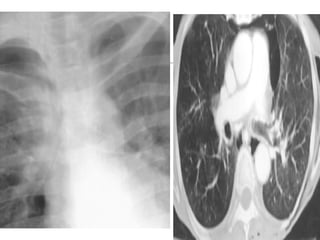

Radiographic Signs of Pneumomediastinum

• 82.

Radiographic Signs ofPneumomediastinum Subcutaneous emphysema Thymic sail sign Pneumoprecardium Ring around the artery sign Tubular artery sign Double bronchial wall sign Continuous diaphragm sign Extrapleural sign Air in the pulmonary ligament